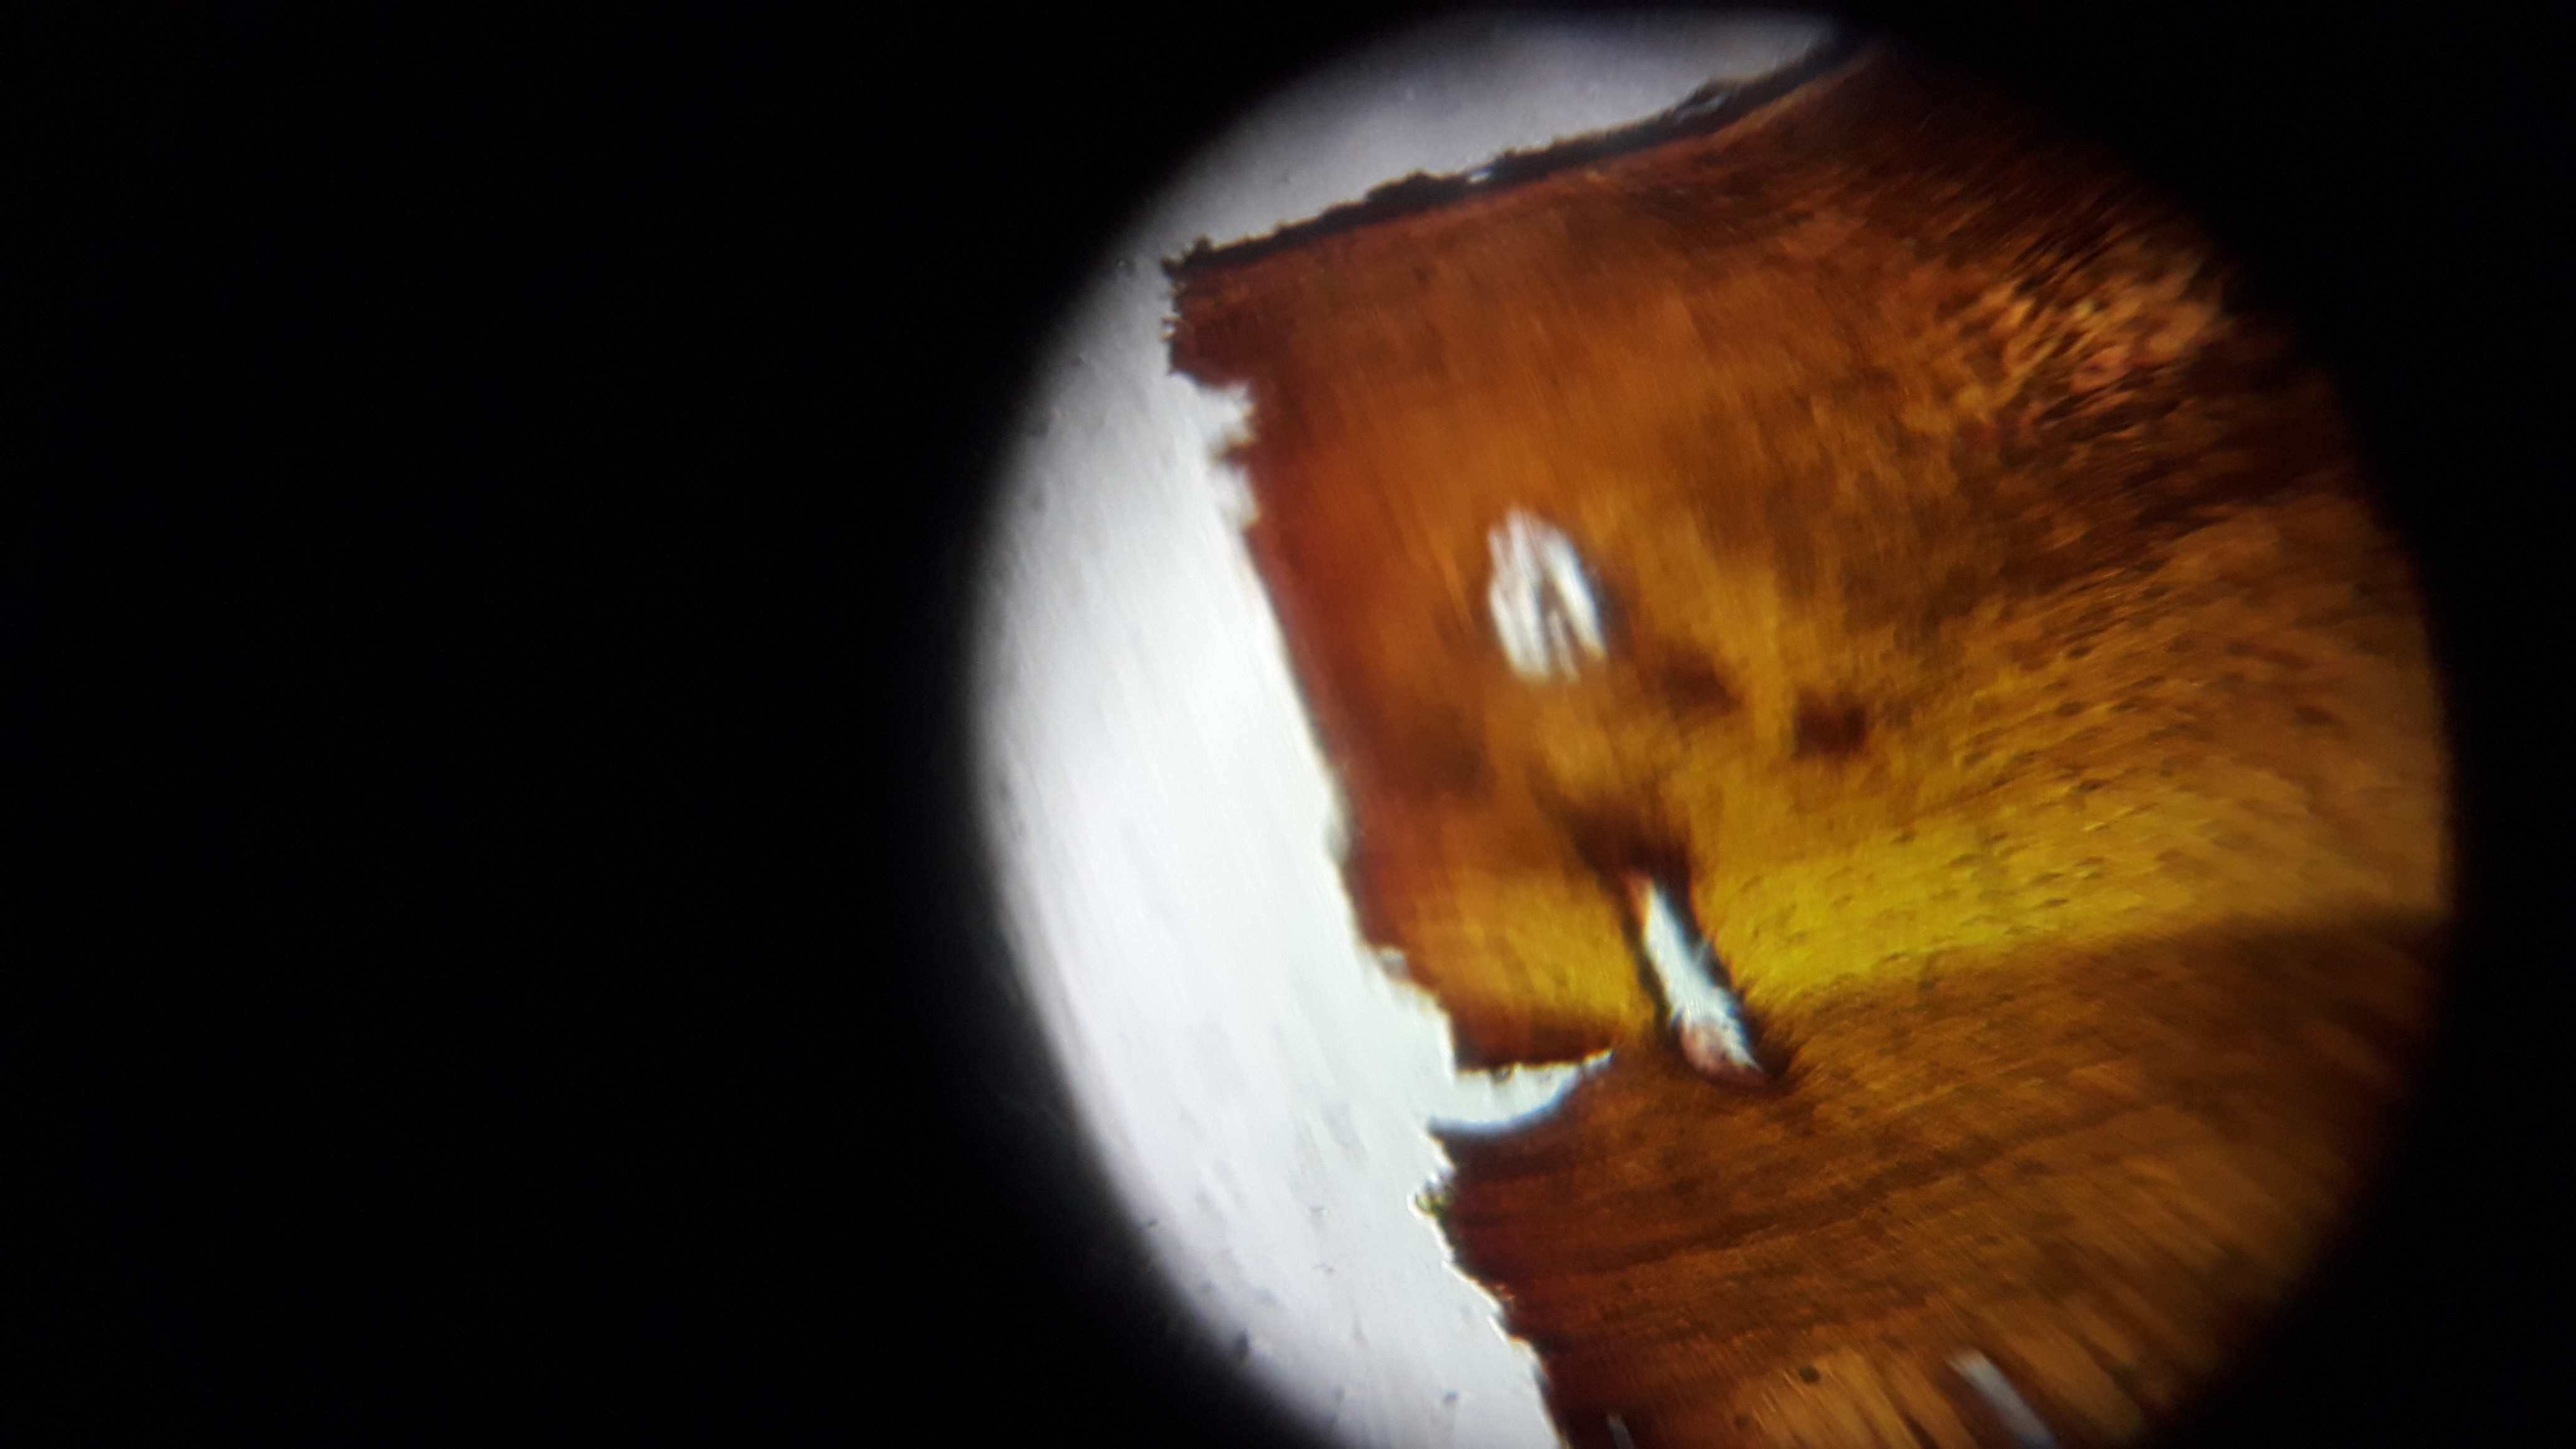

Thumbnail for Bone cell section

Bone cell section